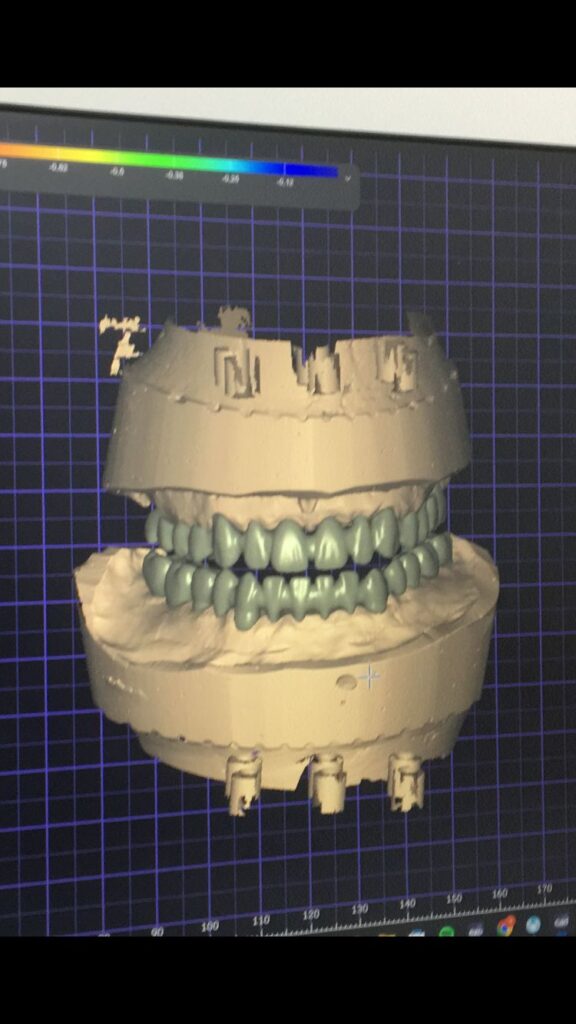

ZIRKONYUM

ZIRKONYUM ALT YAPI

IMPLANT USTU ZIRKONYUM

IMPLANT USTU ZIRKONYUM ALT YAPI